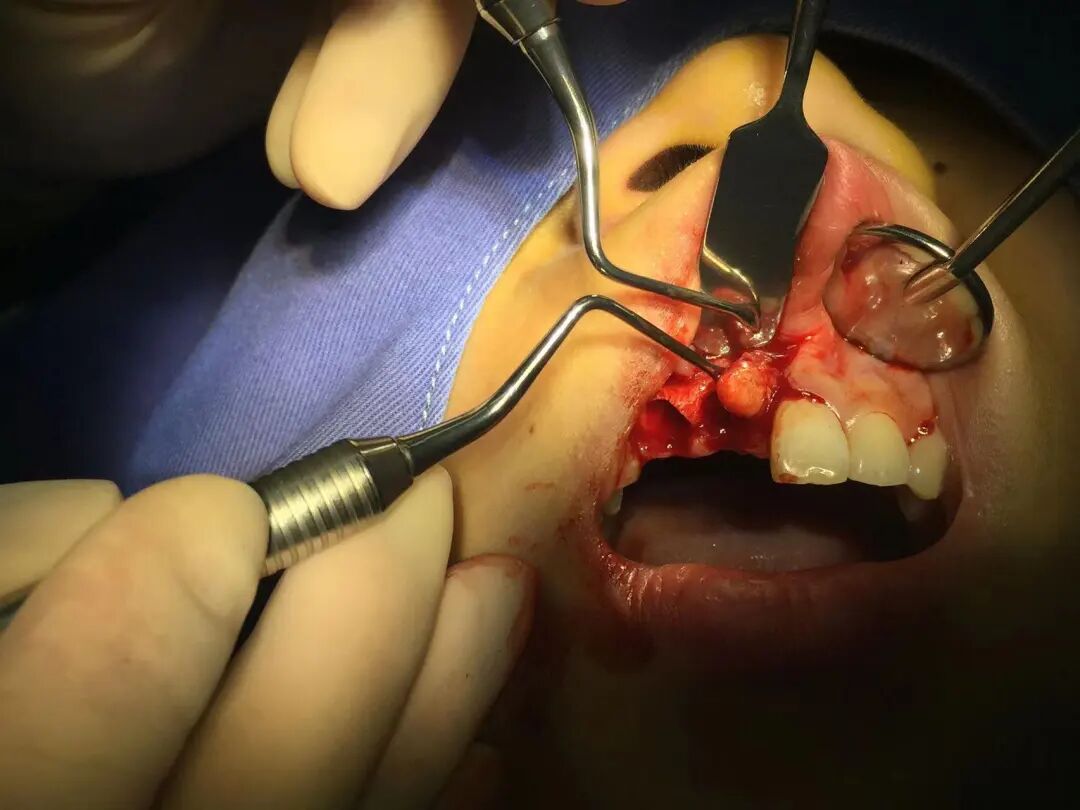

医生给了我两种解决方法,要么保守治疗:保留本牙,在牙龈上开创,把囊肿挖出来再缝合,但有复发的可能性;要么把患齿拔了后把囊肿清理干净,植骨准备种植牙,这样治疗比较彻底(当然清空钱包也很彻底)。

如图所见我选择了第二种。

手术过程 | 图源作者